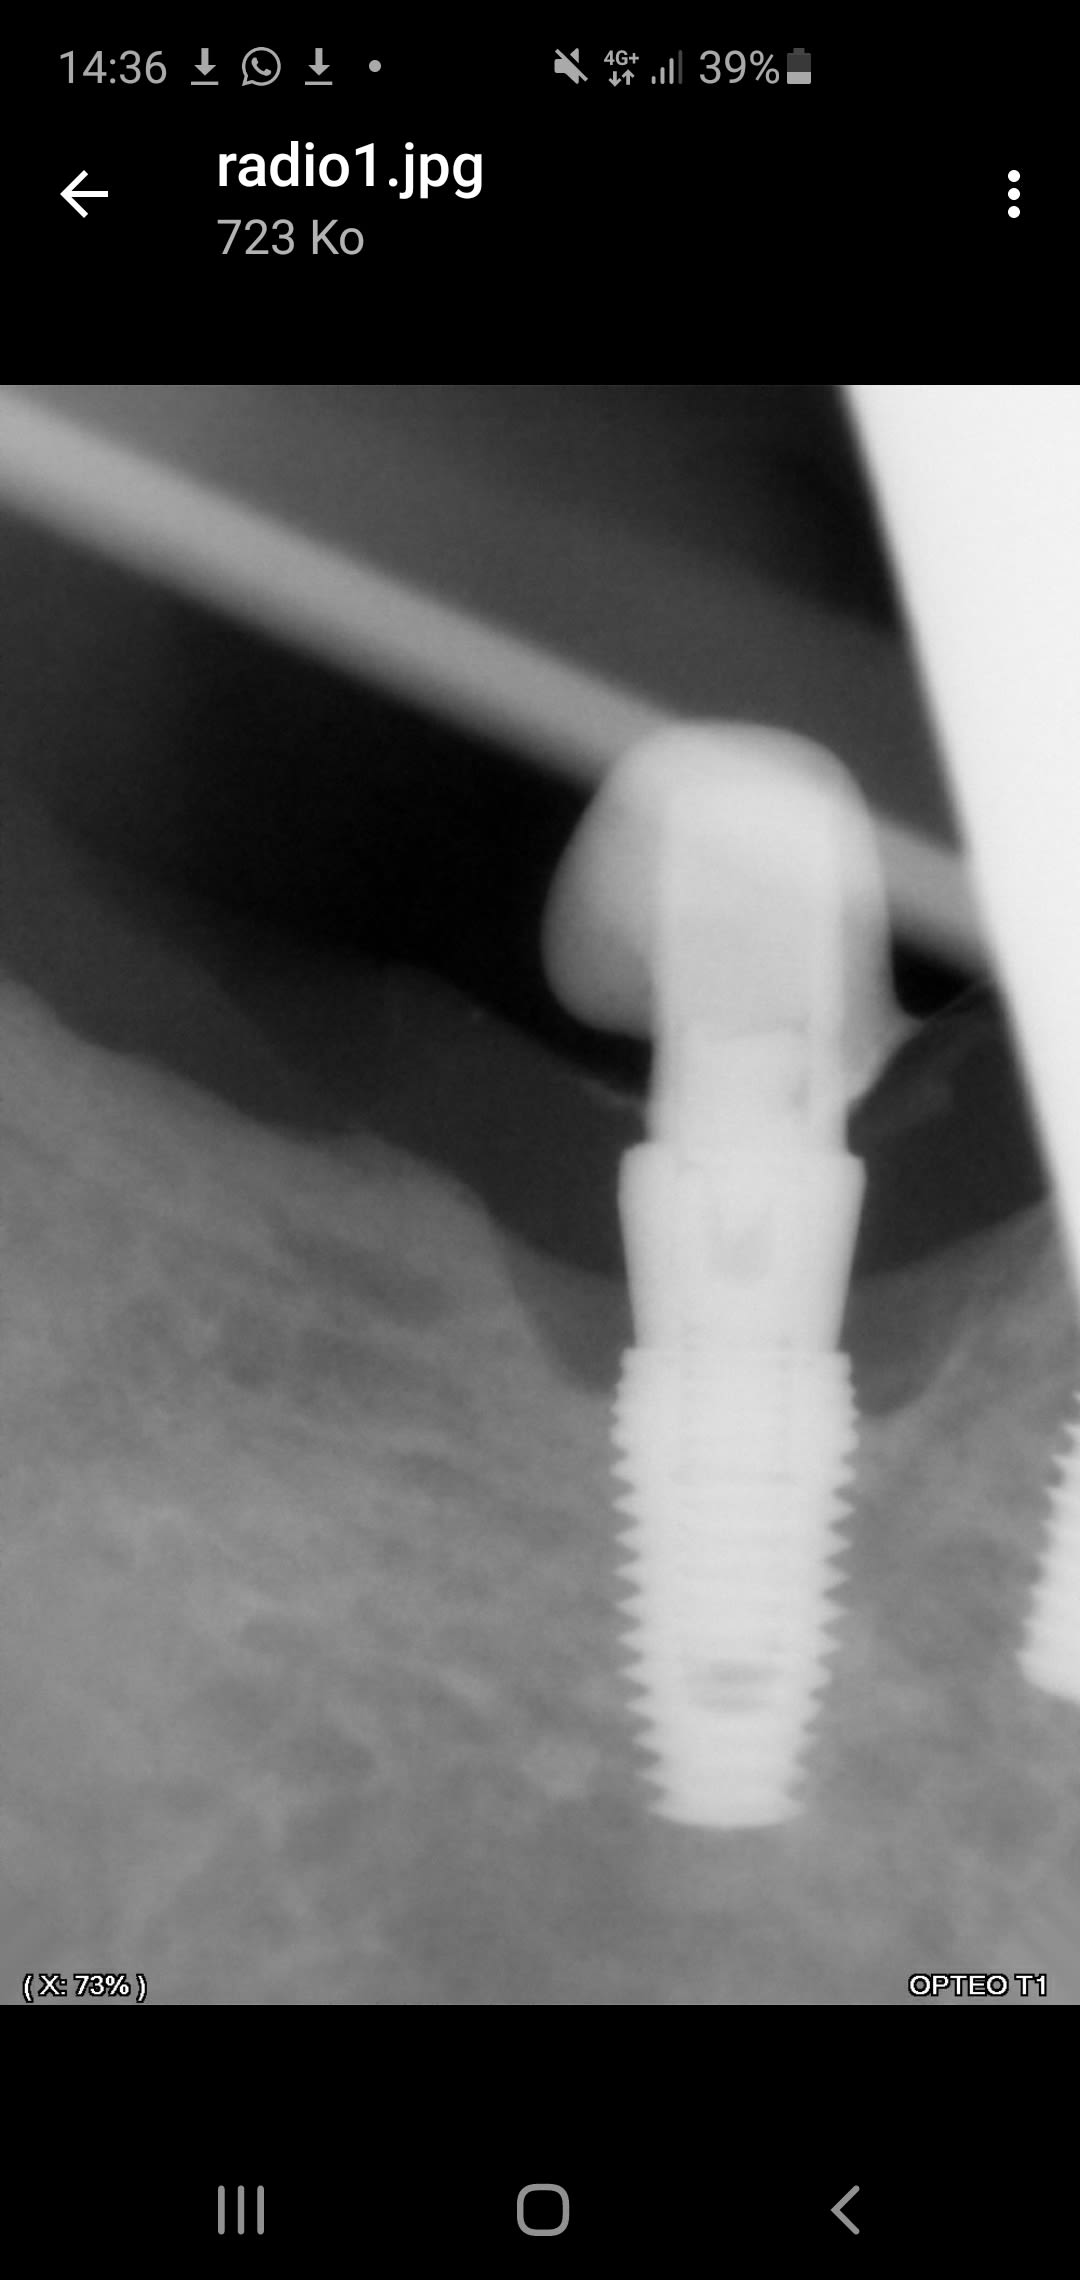

j'ai un doute mais çà me semble être du Neodent drive GM

On dirait qu'il y a un elargissement du diamètre par rapport au col non?

Osstem ?

non pas osstem

Neodent oui tu as un retrait au col plus important pour les implants larges à la manière d'un Nobel active (mais c'est pas lui car les spires sont trop serrées pour que çà soit çà...)

regarde là même si la radio est pourrie

https://whatimplantisthat.com/implants/details/drive-cm

Et les potosses, pourquoi y cratérise ?

Sous crestal, col titane biseauté, plateforme switching...

Y’a trois étages ou c’est mes yeux ?

Une periimplantite ça peut arriver même sur le meilleur implant du monde...

3 étages si tu comptes implant /pilier /couronne oui, sinon c’est tes yeux....

Au fait raeko....un autre implant qui peut matcher avec ton cas...

https://whatimplantisthat.com/implants/details/touareg-wp-2

Hmmm.. ca vrai que ca y ressemble aussi..

Il s agit d un systeme octogonal. Y a que ca qui peut trancher entre toureg et neodent